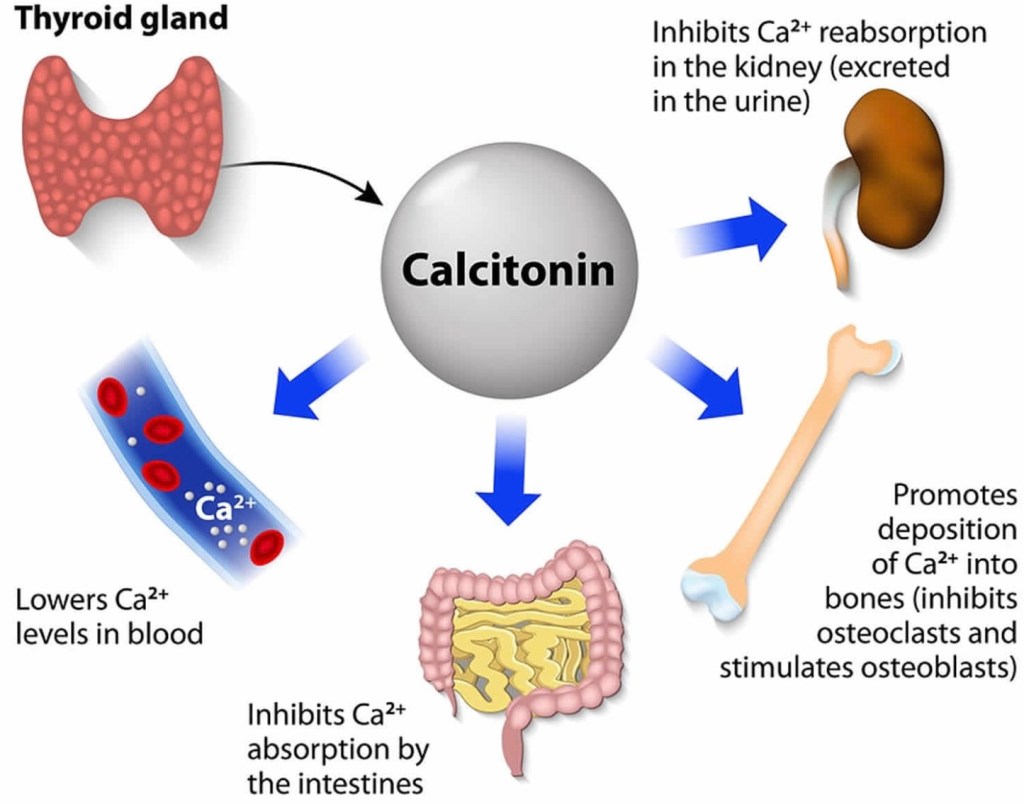

- MTC is different from other types of thyroid cancers (which are derived from thyroid follicular cells – the cells that make thyroid hormone), because it originates from the parafollicular C cells (also called “C cells”) of the thyroid gland. These cells do not make thyroid hormone and instead make a different hormone called calcitonin.

A diagnosis of thyroid cancer is usually made by a fine needle aspiration (FNA) biopsy of a thyroid nodule, or after the nodule is surgically removed. Patients in whom the results of an FNA biopsy (or histopathology) are suggestive or indicative of MTC should be further evaluated with measurement of the proteins calcitonin and carcinoembryonic antigen (CEA) in the blood, which are typically elevated in patients with MTC. These tests are useful to confirm the diagnosis of MTC which can help ensure the surgeon plans the correct surgery, and also serve as tumor markers during long-term follow-up to detect any remaining disease or recurrence of the cancer.

Patients with MTC with very high levels of calcitonin should have imaging prior to surgery to determine whether the tumor has spread to sites outside the thyroid and/or outside the neck. If there is evidence of cancer outside the neck, surgery may be more palliative, aimed at reducing local complications caused by the tumor, rather than completely eliminating all tumor. Other treatment options (external beam radiation, or chemotherapy) may need to be used together with surgery after careful discussion with the patient.

Measurement of calcitonin and CEA are a necessary routine part of the follow-up of patients with MTC. Following thyroidectomy, it is hoped that calcitonin levels will be essentially undetectable for life. A detectable or rising calcitonin level should raise suspicion for possible cancer recurrence. Detectable calcitonin levels may require additional tests.